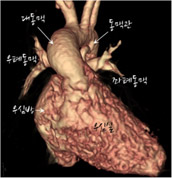

CT로 본 대동맥근 전위술의 수술 전후 모습

- 정면에서 본 모습

[사진4] 수술 전 -

[사진5] 수술 후

수술 전에 대동맥이 심장 앞쪽에서 기시하는 것을 관찰할 수 있습니다. 수술 후 대동맥 자체가 후방으로 이동했고 폐동맥으로 lecompte maneuver를 해서 대동맥 앞으로 옮기고 좌,우폐동맥이 팔을 벌린 모양을 하고 있습니다. 폐동맥이 이전의 대동맥 자리에 위치해 전방의 흉골에 덜 눌리는 모양입니다.